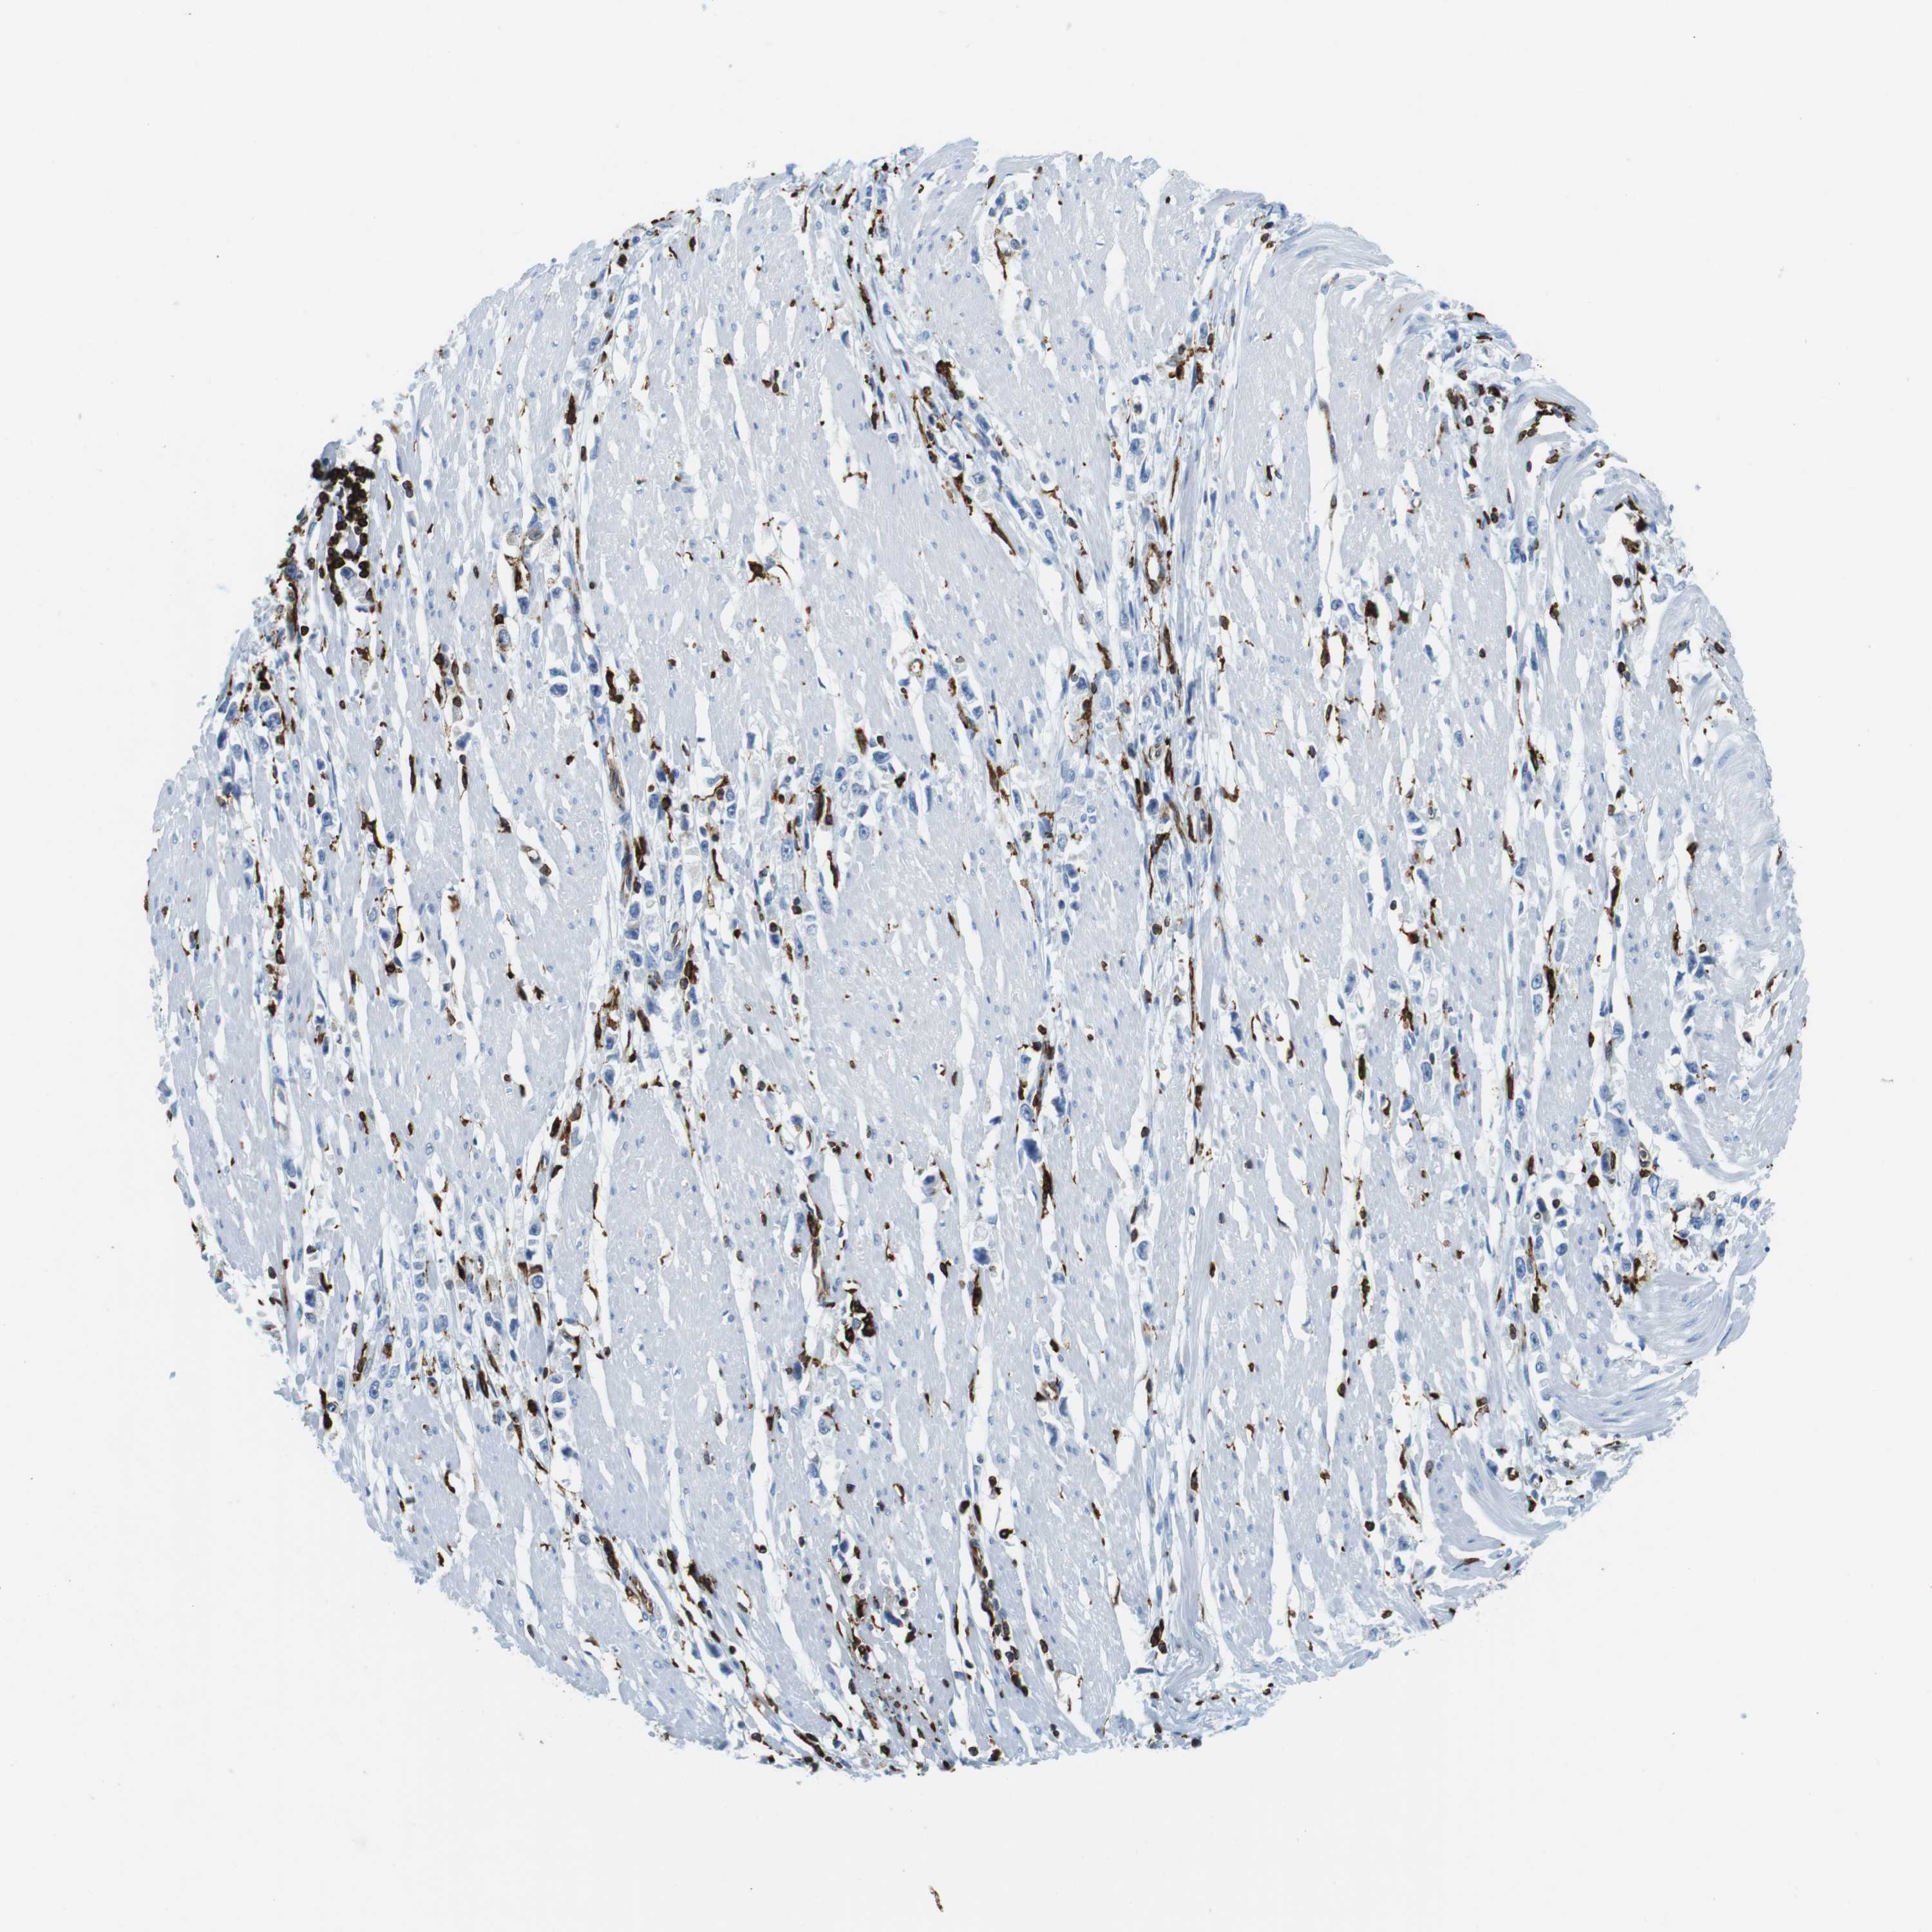

STOMACH CANCER - Protein expressioni

A mouse-over function shows sample information and annotation data. Click on an image to view it in a full screen mode. Samples can be filtered based on level of antibody staining by selecting one or several of the following categories: high, medium, low and not detected. The assay and annotation is described here.

Note that samples used for immunohistochemistry by the Human Protein Atlas do not correspond to samples in the TCGA dataset.

Antibody stainingi

Antibody staining in the annotated cell types in the current human tissue is reported as not detected, low, medium, or high, based on conventional immunohistochemistry profiling in selected tissues. This score is based on the combination of the staining intensity and fraction of stained cells.

Each image is clickable and will lead to virtual microscopy that enables deeper exploration of all samples and also displays staining intensity scores, fraction scores and subcellular localization as well as patient and tissue information for each sample.

Antibody CAB016084

Staining

High

Medium

Low

Not detected

Intensity

Strong

Moderate

Weak

Negative

Quantity

>75%

75%-25%

<25%

None

Location

Nuclear

Cytoplasmic/membranous

Cytoplasmic/membranous,nuclear

Adenocarcinoma, NOS